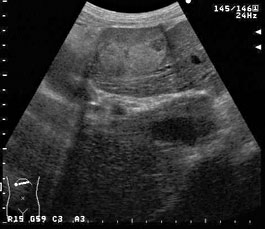

径1.5cmの低エコー腫瘤の一部に高エコー部分を含んでいる。 |

高エコー結節の経過観察中にサイズの増大が認められ、内部に低エコー部が出現した。 |